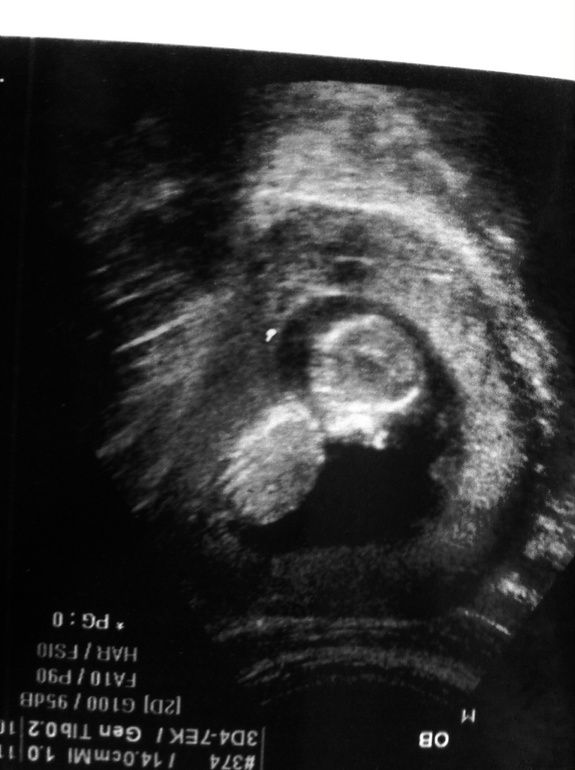

Моя дочка)))

Сделали Узи, сказали 70% что девочка.

Копчико-теменной размер -6,1 см.

Срок -13 н. 1 дн.

Вот моя кроха)))